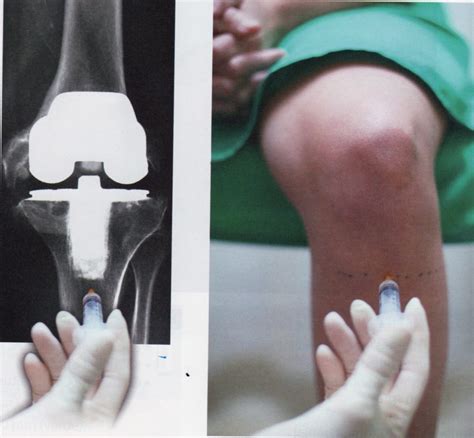

Tiempo De Baja Laboral Por Protesis De Rodilla, ¿Cuánto tiempo se tarda en volver a la vida normal tras una operación de de prótesis de rodilla, 679.69 kB, 00:29, 44,802, Solcot, traumatología Madrid, 2017-10-24T11:18:07.000000Z, 3, Prótesis de rodilla: Todo sobre la operación y la recuperación, okdiario.com, 2816 x 1872, jpeg, WebEl tiempo medio habitual de una baja laboral por prótesis de rodilla es de 6 a 12 semanas. Pacientes con trabajos menos demandantes pueden volver a trabajar tan pronto hagan. WebTrabajo de camarero cuanto tiempo estaré de baja por operacion de protesis de rodilla? Llevo un año con prótesis de cadera,no tengo dolor.puedo volver a mi trabajo de. WebEl reemplazo total de rodilla tradicional implica una incisión de 7-8″ sobre la rodilla, una estancia en el hospital de 3-5 días y un periodo de recuperación (durante el., 20, tiempo-de-baja-laboral-por-protesis-de-rodilla, Novedades y Muebles WebEl tiempo medio habitual de una baja laboral por prótesis de rodilla es de 6 a 12 semanas. Pacientes con trabajos menos demandantes pueden volver a trabajar tan pronto hagan. WebTrabajo de camarero cuanto tiempo estaré de baja por operacion de protesis de rodilla? Llevo un año con prótesis de cadera,no tengo dolor.puedo volver a mi trabajo de. WebEl reemplazo total de rodilla tradicional implica una incisión de 7-8″ sobre la rodilla, una estancia en el hospital de 3-5 días y un periodo de recuperación (durante el.

WebNormalmente, se pueden retomar las actividades cotidianas a las 3 o 6 semanas tras la cirugía. El programa de ejercicio físico de la recuperación en casa. WebEl tiempo de recuperación de la artroscopia de rodilla. La artroscopia de rodilla es una intervención que tiene una duración aproximada de 30 minutos. Suele realizarse. WebEl tiempo de baja laboral después de una artroscopia de rodilla depende de la extensión de la cirugía y de la condición de la rodilla antes de la operación. En. WebNo. Los partes de confirmación ya no los entregan semanalmente, sino que el alta y la baja se dan a la vez en los procesos de menos de 5 días y en plazos más. WebLa restauración tras una operación de prótesis de rodilla, acostumbra a requerir de ingreso hospitalario de entre 3 y 5 días. El paciente comienza a pasear un. WebEn general las prótesis de rodilla no tienen una duración publicada tan larga como las de cadera pero su supervivencia sigue siendo excelente. Por lo tanto aunque también se intentan otras alternativas para retrasarla, al final, la limitación funcional y el dolor marcarán el momento de la operación, no la edad. WebLa recuperación puede alargarse más de un año, que es cuando a buen seguro volverás a tener tanto la movilidad como la fuerza muscular previas a tener problemas en la zona. Estos son los cuidados básicos que debes poner en práctica en tu hogar: Toma la medicación pautada por tu médico.